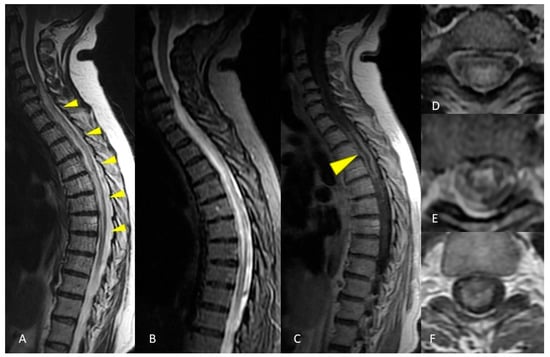

2.2. Case Presentation 2